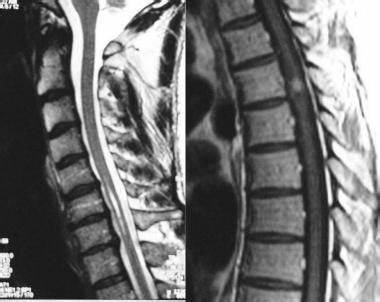

髓内脊髓肿瘤(IMSCTs),如下图所示,是指硬膜内 脊髓肿瘤 的一个亚群,由脊髓内的细胞产生,与相邻结构如神经根或脑膜相对。它们比脑瘤少见得多,据认为占中枢神经系统全部固有肿...

大多数脊髓髓内肿瘤患者起初可以通过尝试切除来治疗。不幸的是,那些不能行总切除或次全切除的患者,只能选择放疗和化疗...